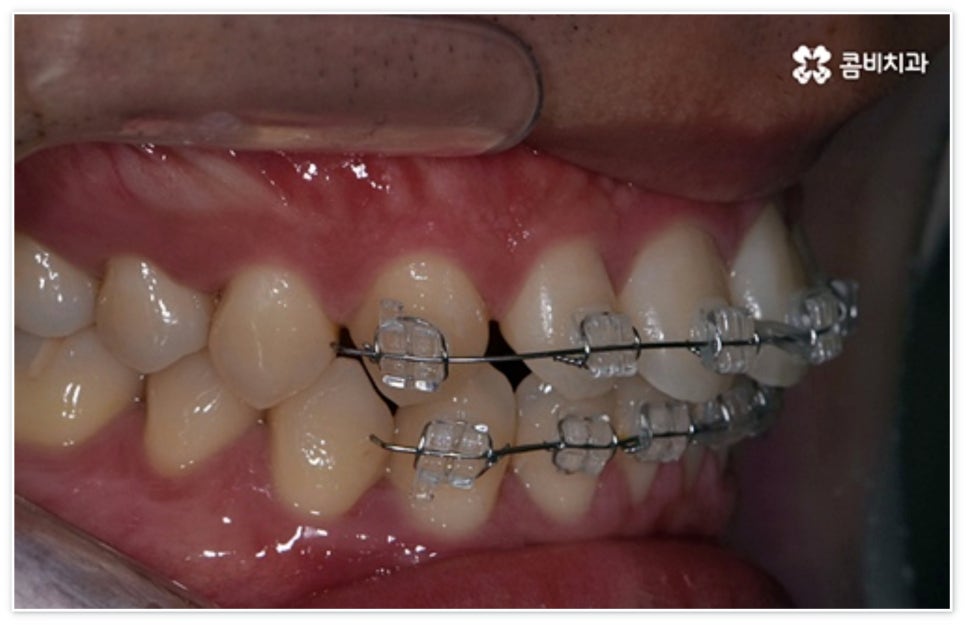

환자분들에 따라 다르지만 통상적으로 전체 교정이 1년에서 2년 반 정도 소요된다면 부분 교정은 6~8개월 정도로 기간 단축이 가능하여 치료에 대한 부담을 줄일 수 있으며 대부분 발치 과정 없이 필요한 부위에만 브라켓을 부착하는 만큼 불편함이 적고 구강 관리도 용이한 편이니 (사진에서 살펴볼 수 있는 케이스) 이에 대해서 자세히 알아보시면 좋을 거예요. 물론 누구나 가능한 것은 아니고 개인의 구강 상태에 따라 진행을 해야 하므로 꼼꼼한 검진과 충분한 상담부터 받아보시길 권유드리고 있습니다.